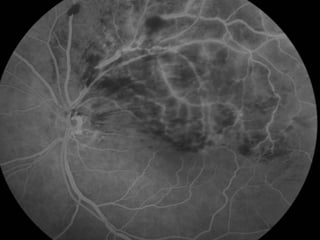

Angiografia 10/02/2009

• ANGIOGRAFICO

– Define edema macular, a perfusão da rede capilar para-foveal e a presença de

neovasos.

– Mostra o retardo artério-venoso na arcada comprometida e a presença de

áreas isquêmicas e de vazamento tardio.